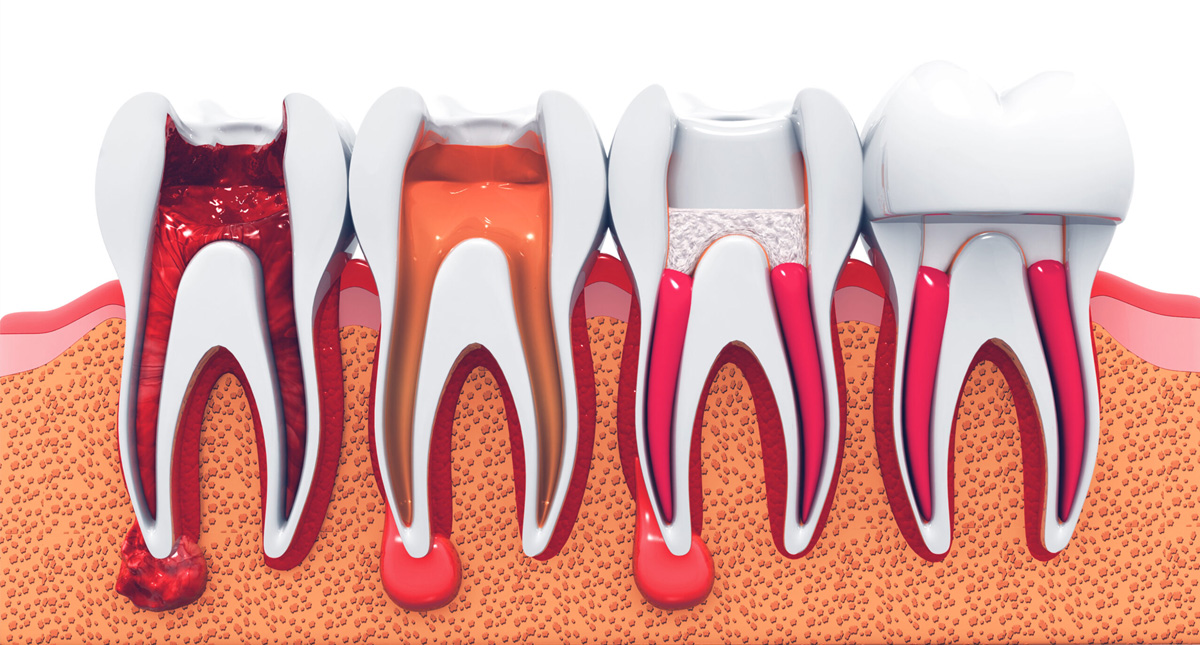

根管治療が必要な歯の症状

虫歯が神経に到達した場合や既に根の治療をしてある歯が再感染をおこした場合に治療が必要となります。

神経に虫歯が到達すると、ほとんどの場合激しい痛みがでます。何もしていなくてもズキズキしたり温かい物で痛みが大きくなります。痛み止めを飲んでもひかないほどの痛みの場合が多いです。これは神経が細菌感染を起こすため出る痛みです。そのまま放置するとやがて痛みはなくなりますが、これは治ったわけではなく感染して神経が死滅するため痛みがなくなります。感染したまま放置すればするほど根の中の菌が増え、根管治療による成功率も下がります。

神経が死滅して痛みが消えた後も放置し続けると、中の菌がさらに増えて歯の根の先に膿がたまっていきます。膿がたまると噛んだ時や歯茎を押した時に痛みが出たり、歯茎にできものができます。

きちんと根管治療をしなかった場合の例

歯の根管にいれる薬がきれいに入っていなかったり、隠れた根管がみつけられずお掃除できていなかったりすると、そこに菌がたまり膿をつくってしまう場合があります。

また根管治療後にいれる被せものの精度も、将来的に膿ができないようにする上でかなり重要であることがわかっています。

抜歯しなければならないケース

歯の根っこが割れてしまっているケースは抜歯の適応となります。